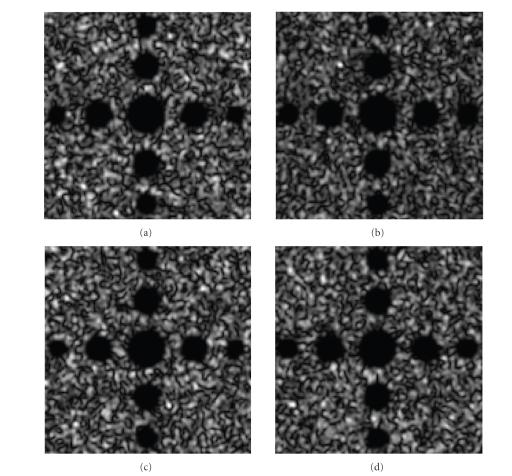

The reconstruction of 3D ultrasound (US) images from mechanically registered, but otherwise irregularly positioned, B-scan slices is of great interest in image guided therapy procedures. Conventional 3D ultrasound algorithms have low computational complexity, but the reconstructed volume suffers from severe speckle contamination. Furthermore, the current method cannot reconstruct uniform high-resolution data from several low-resolution B-scans. In this paper, the minimum mean-squared error (MMSE) method is applied to 3D ultrasound reconstruction. Data redundancies due to overlapping samples as well as correlation of the target and speckle are naturally accounted for in the MMSE reconstruction algorithm. Thus, the reconstruction process unifies the interpolation and spatial compounding. Simulation results for synthetic US images are presented to demonstrate the excellent reconstruction.

从机械配准但位置不规则的B扫描切片重建三维超声(US)图像在图像引导治疗程序中具有重要意义。传统的三维超声算法计算复杂度低,但重建的体积受到严重的斑点污染。此外,当前方法无法从多个低分辨率B扫描重建均匀的高分辨率数据。本文将最小均方误差(MMSE)方法应用于三维超声重建。MMSE重建算法自然地考虑了由于重叠样本以及目标与斑点的相关性而产生的数据冗余。因此,重建过程统一了插值和空间复合。给出了合成超声图像的模拟结果,以证明出色的重建效果。